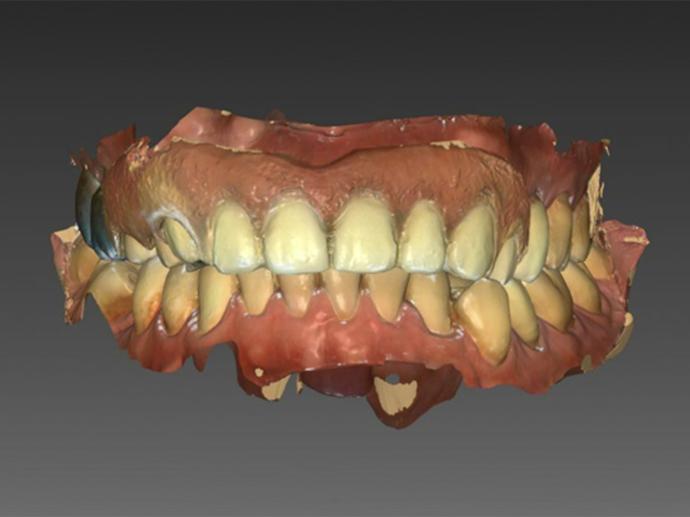

口掃機掃瞄,並設計完成的假牙型態,再決定植牙的植入位置及角度